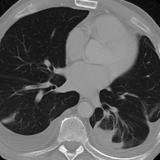

Microatelectasis (under debate)